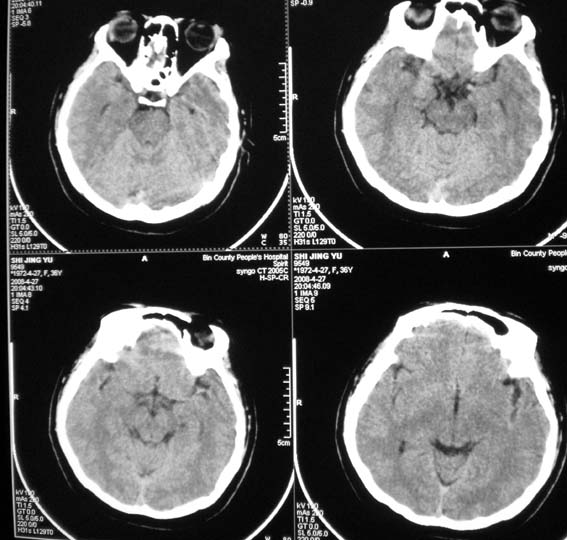

标题: CT13124:女,36岁,常短暂性意识丧失。 [打印本页]

女,36岁,常短暂性意识丧失。

颅脑ct平扫未见明显异常。

右顶部放射冠部白质内异常灰质团块影 考虑灰质移位症可能

患者短暂性意识丧失考虑为癫痫小发作

另外要注意患者ecg或holter检查,以除外心源性晕厥可能

鞍上池右侧旁脑质内见团块稍高密度影,建议mr检查。